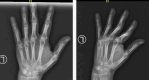

Case presentation: A 46-year-old right-handed Asian woman presented to the orthopedic polyclinic complaining of a painless mass on the palm of her left hand for four years. Physical examination revealed a solid, mobile, non-tender mass with well-defined margins. Radiographic imaging showed a well-circumscribed soft tissue mass with fat and central calcification. The patient underwent surgical excision, and a histopathological examination confirmed the osteolipoma. A six-month follow-up revealed no recurrence, and the patient could resume her daily activities.